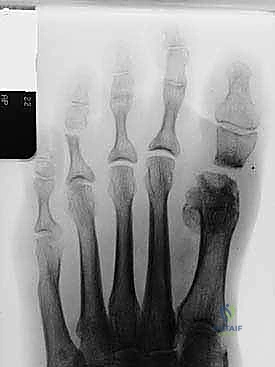

- التصوير بالأشعة السينية (X-rays): صور في وضعية الوقوف (تحمل الوزن) من زوايا متعددة لقياس زوايا التشوه بدقة وحساب مقدار الطول المفقود.

- الأشعة: يتم إجراء أول صورة أشعة سينية للمتابعة للتأكد من ثبات المسامير وبدء عملية الالتئام.

- إذا أظهرت الأشعة السينية علامات قوية لاندماج الطعم العظمي، يسمح د. هطيف بالتحميل التدريجي لوزن الجسم بالكامل أثناء ارتداء الحذاء الطبي الصلب.